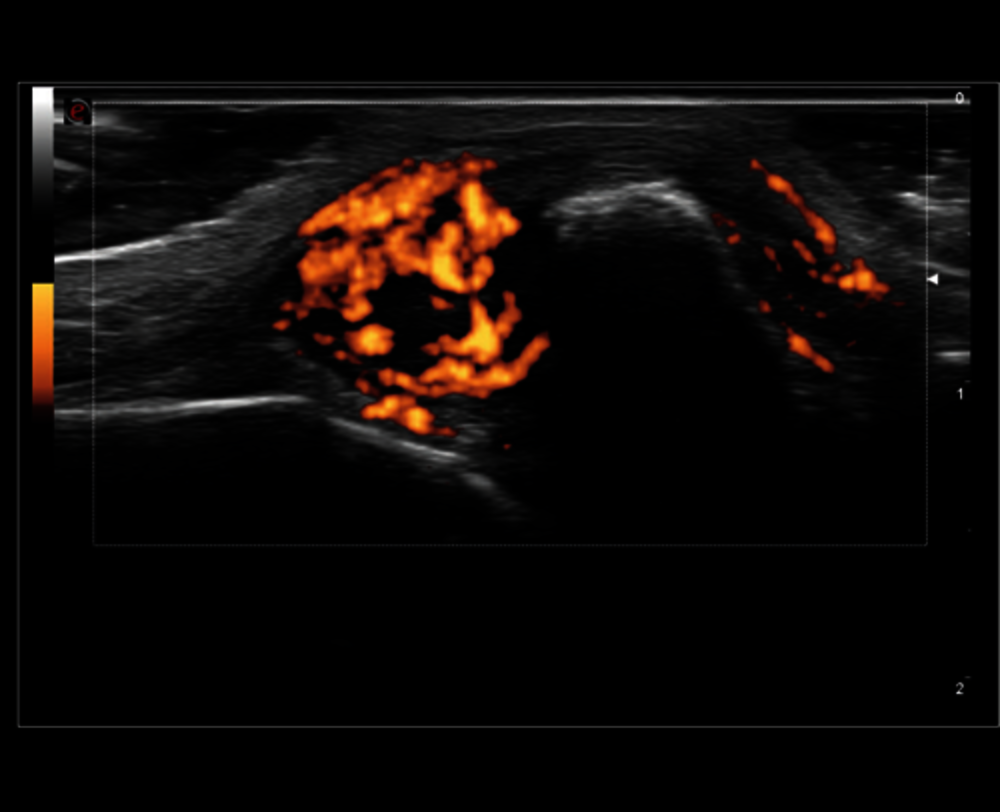

Výkonový Doppler v oblasti zánětu akutní polyartritidy se sondou 18 MHz